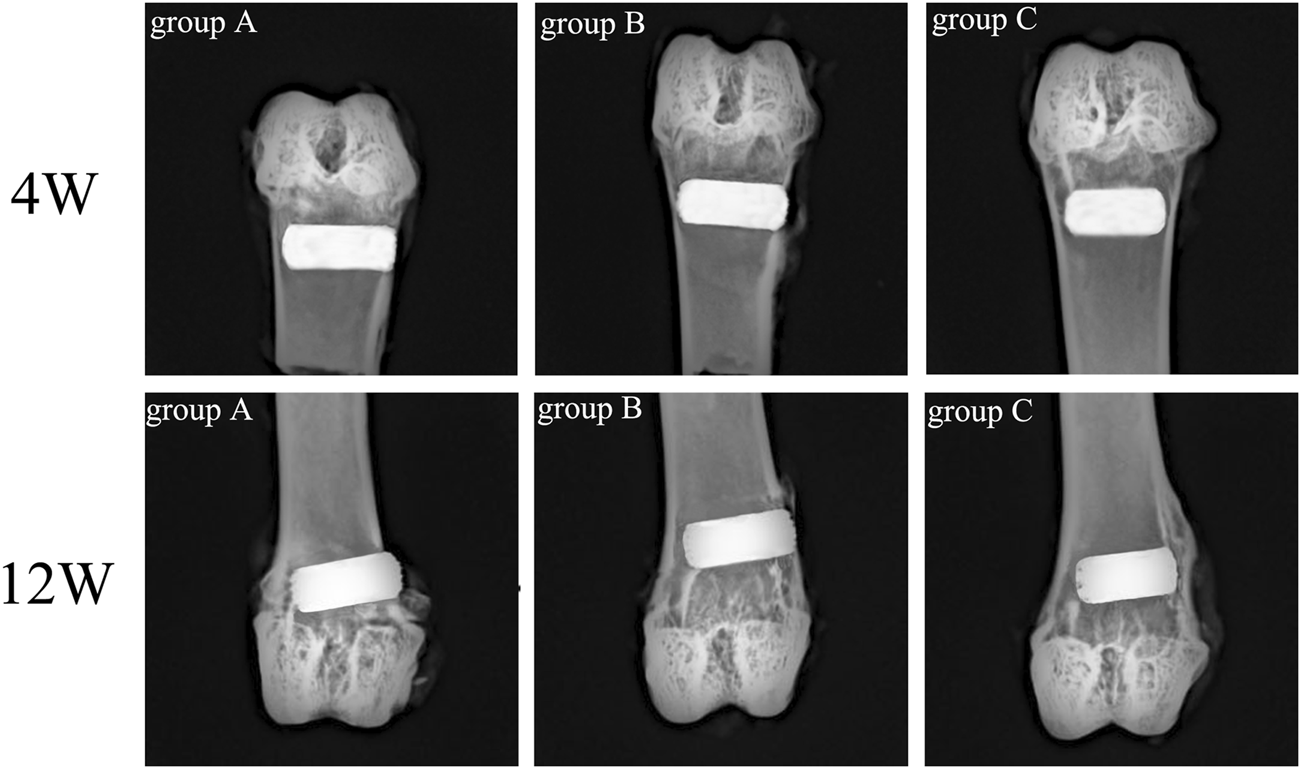

Rabbit femur samples were obtained on the 4th and 12th week after scaffold implantation, and an X-ray plane inspection was performed after fixation. Figure 11 illustrated that all implanted scaffolds were in a good position, without loosening, falling, or dislocating. Also, no inflammatory reaction and infection were detected in the samples.

FIGURE 11

X-ray examination of rabbit femur after scaffold implantation in each group.